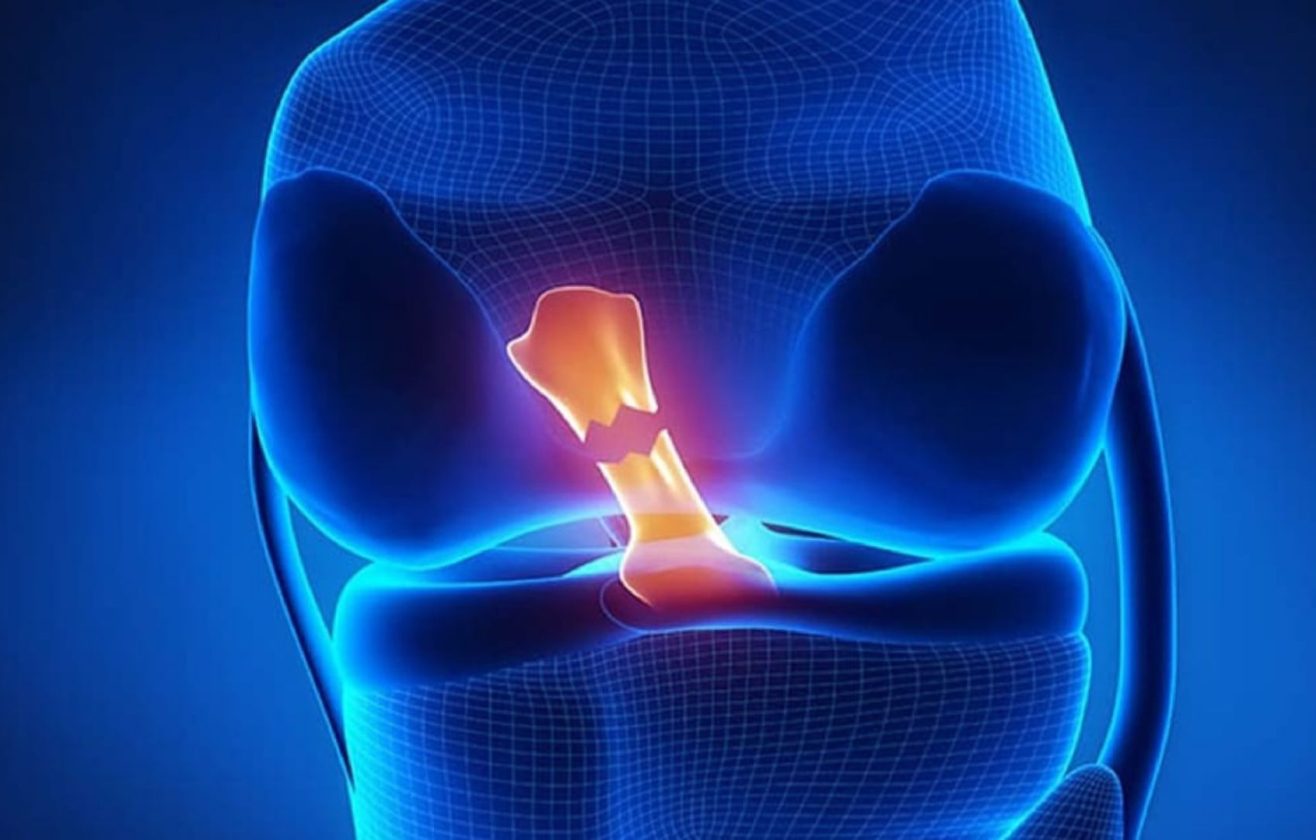

Ön Çapraz Bağ Nedir?

Ön çapraz bağ, diz ekleminde femur (uyluk kemiği) ve tibia (kaval kemiği) arasında uzanan güçlü bir bağdır. Bu bağ, diz eklemine öne ve yana doğru olan aşırı hareketleri sınırlayarak stabilite sağlar ve dizin rotasyon hareketlerini kontrol eder.

Böylece spor ve günlük aktivitelerde dengenin korunmasına yardımcı olur.